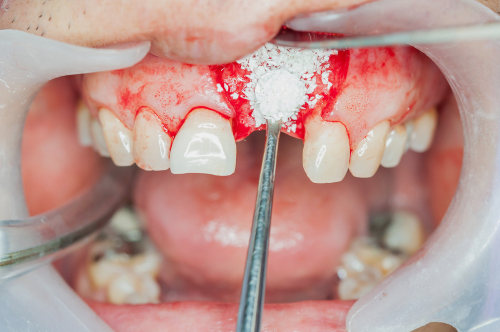

Костные пластинки

• Костные пластики (рассчитывается индивидуально в зависимости от клин. случая , точный план лечения можно получить только после консультации)

от 12 000 ₽